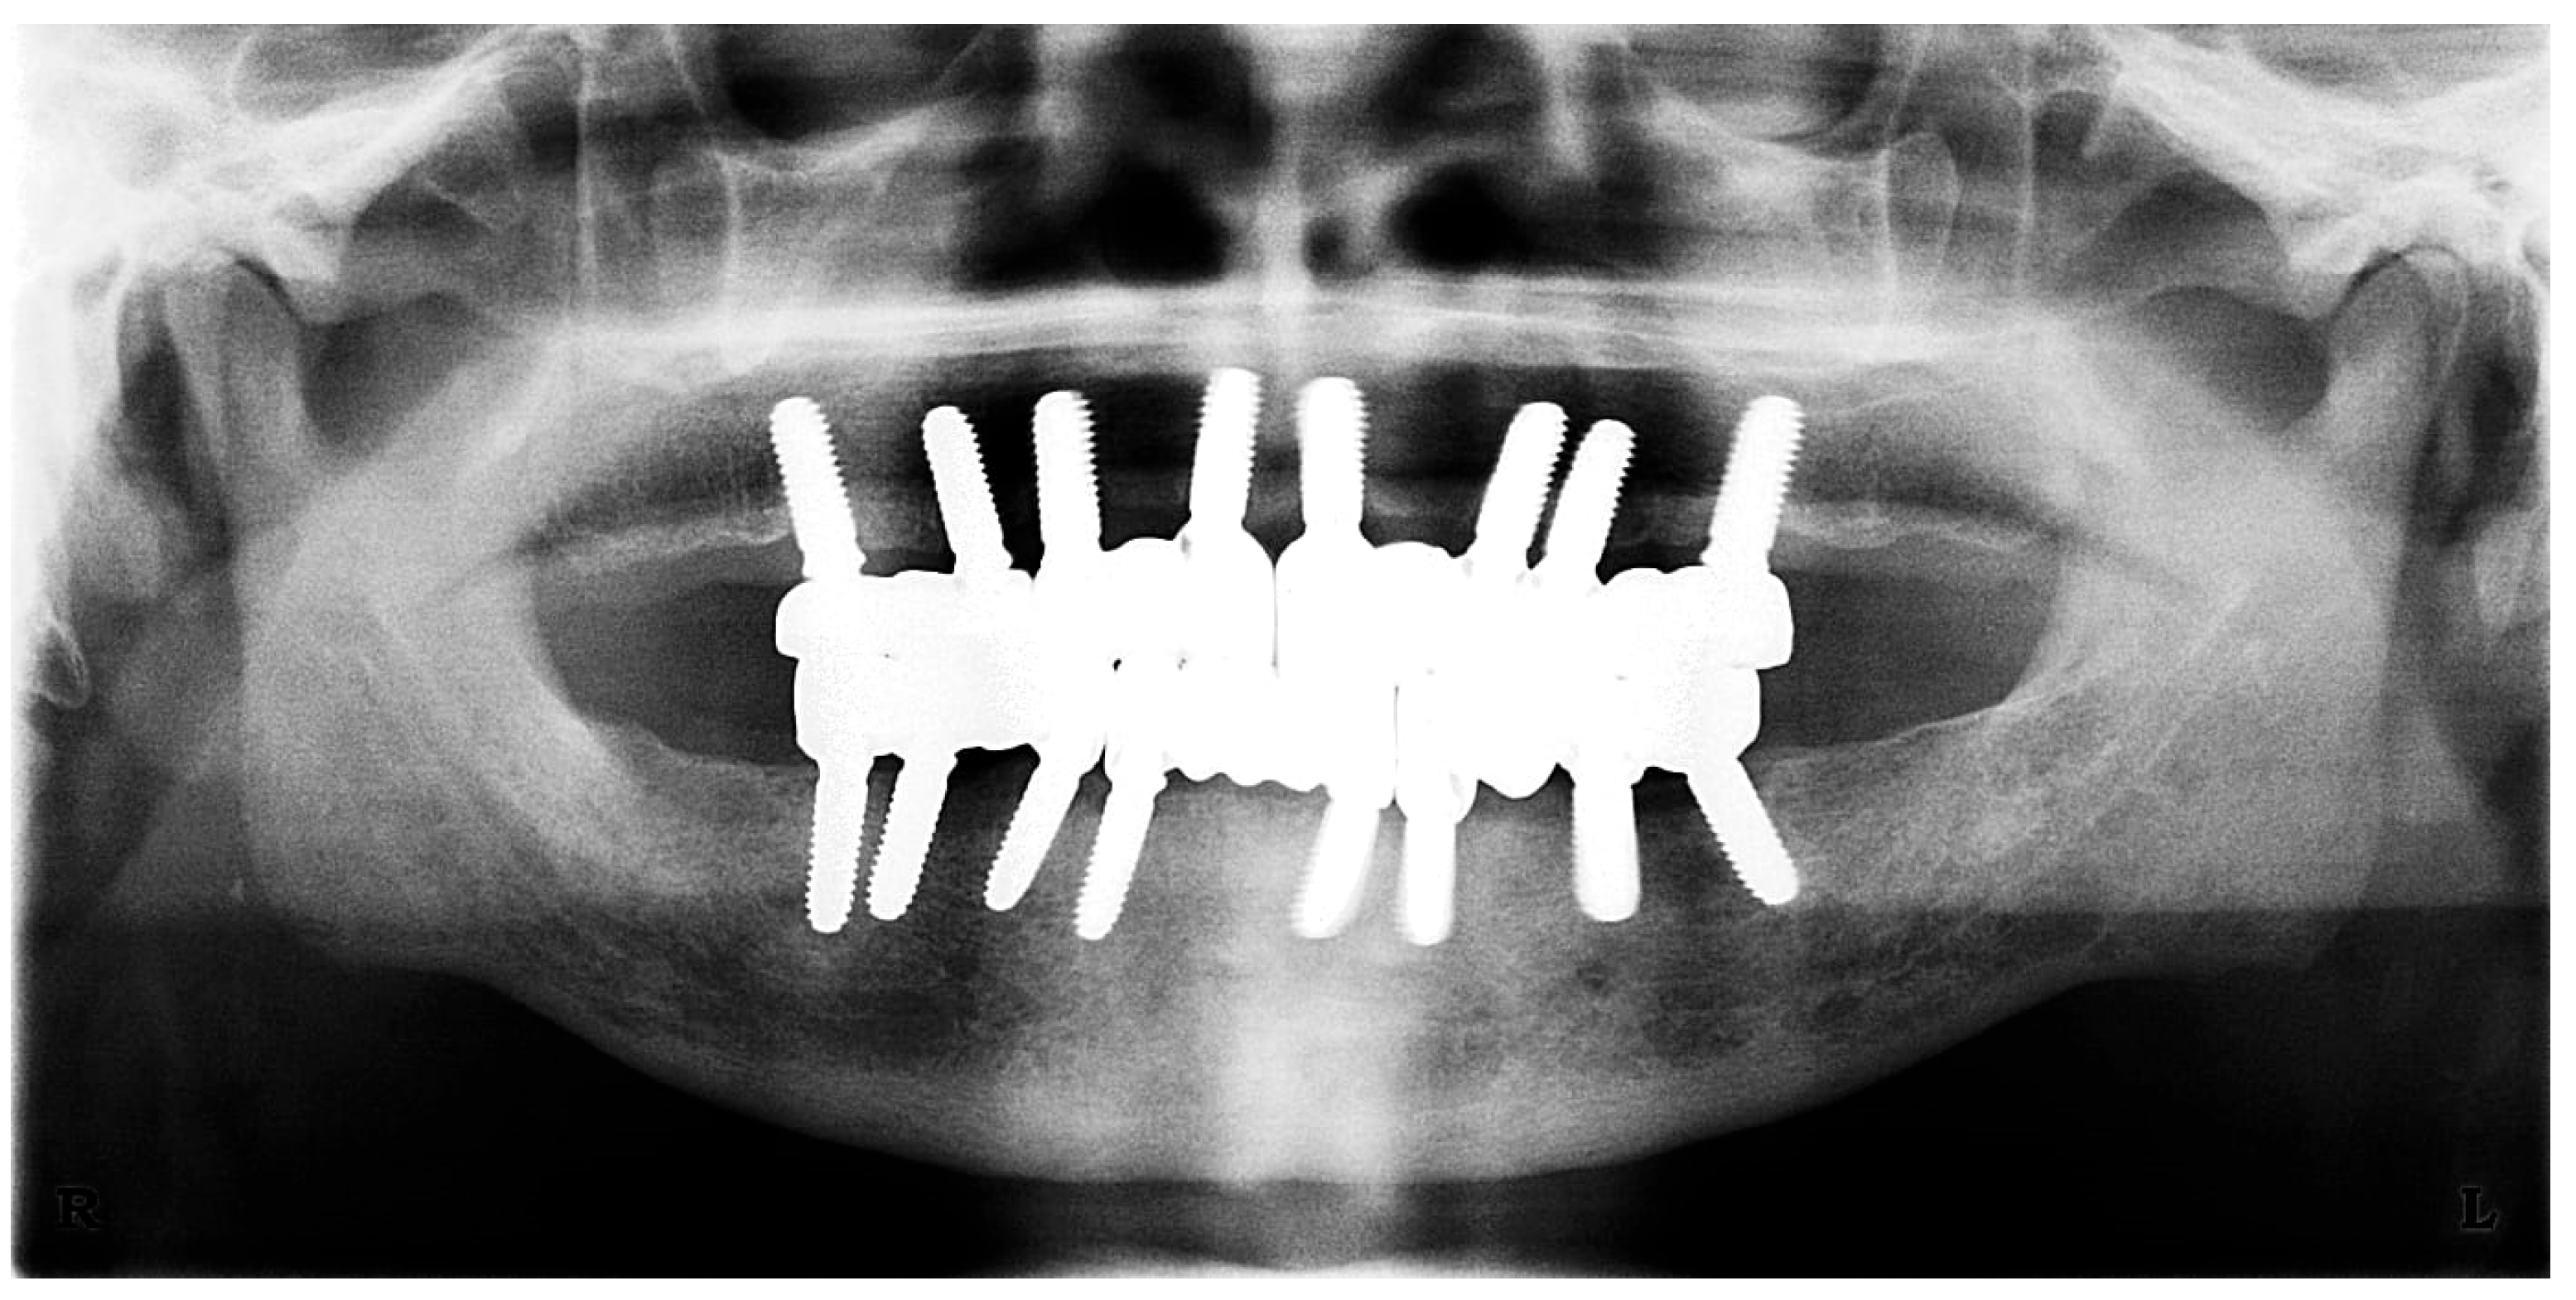

A cone–beam computed tomography (CBCT) scan was performed on the patient with the dentures in situ, providing visualizations of the gutta–percha markers and the alveolar bone’s anatomical dimensions (Figure 5).

Figure 5. CT scan showing the radiopaque gutta–percha cones inserted in the dentures, which mark the locations of the intended dental implants: voxel size 150, voltage 90 kV, current 4 mA, exposure time 15 s.